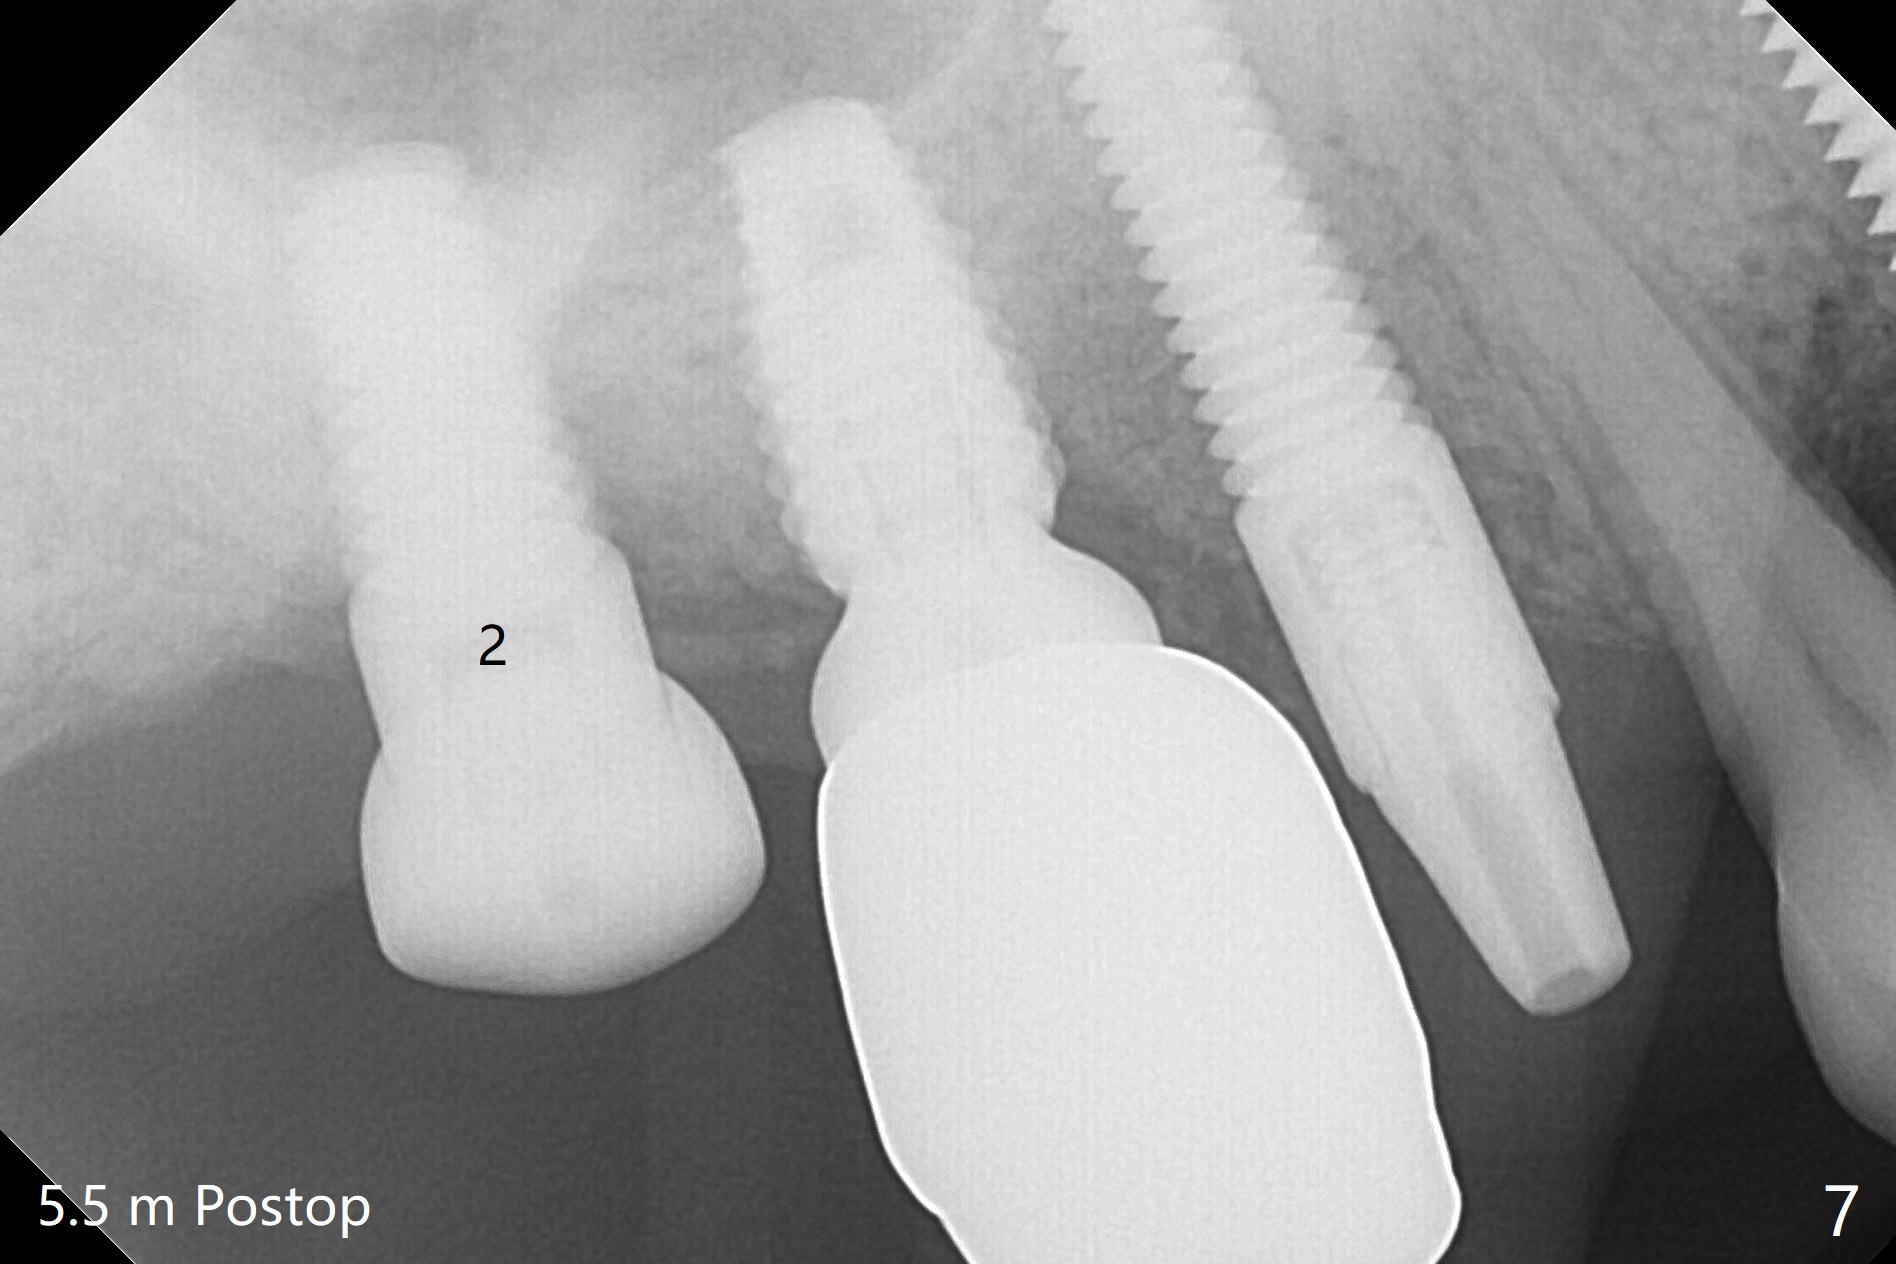

After osteotomy using bone-level implant guide at #4, the crown and abutment at #3 has to be removed to place a 4x14 mm tissue-level dummy implant because of the narrow space of #4 and implant placement angulation (Fig.1). Following initial placement of a final 4x17 mm implant and bone graft (Fig.2 *), the crown and abutment of #3 and the guide are reseated for correct implant trajectory. The guide has to be removed for final depth control. With the same mode, a 5x17 mm tissue-level tap is used at #2 following bone-level osteotomy with guide. A 5x14 mm tissue-level implant is placed with >50 Ncm (later placed deeper), while more bone graft is inserted mesial of #4 implant with a 3.5x5 mm abutment (Fig.3 *). Bone graft is introduced into the sinus using guided sinus lift kit (Fig.4,5 (CT sagittal and coronal sections)) * (D: distal, P: palatal)). The coronal half of the implant at #4 is covered by bone graft (Fig.6 *) buccal (B) and palatal within the deep socket. The implants at #2 and 4 seem to have osteointegrated nearly 5.5 months postop (Fig.7,8 (BW)). A 4.5x5 mm unipost is later placed at #2 with long chamfer margin. It appears that the abutment at #3 is wide. The hex is worn. It changes to a 5.5x7(4) mm one. After abutment adjustment for parallelism, a provisional FPD is fabricated. The latter will be adjusted for papilla formation between implants to reduce food impaction.